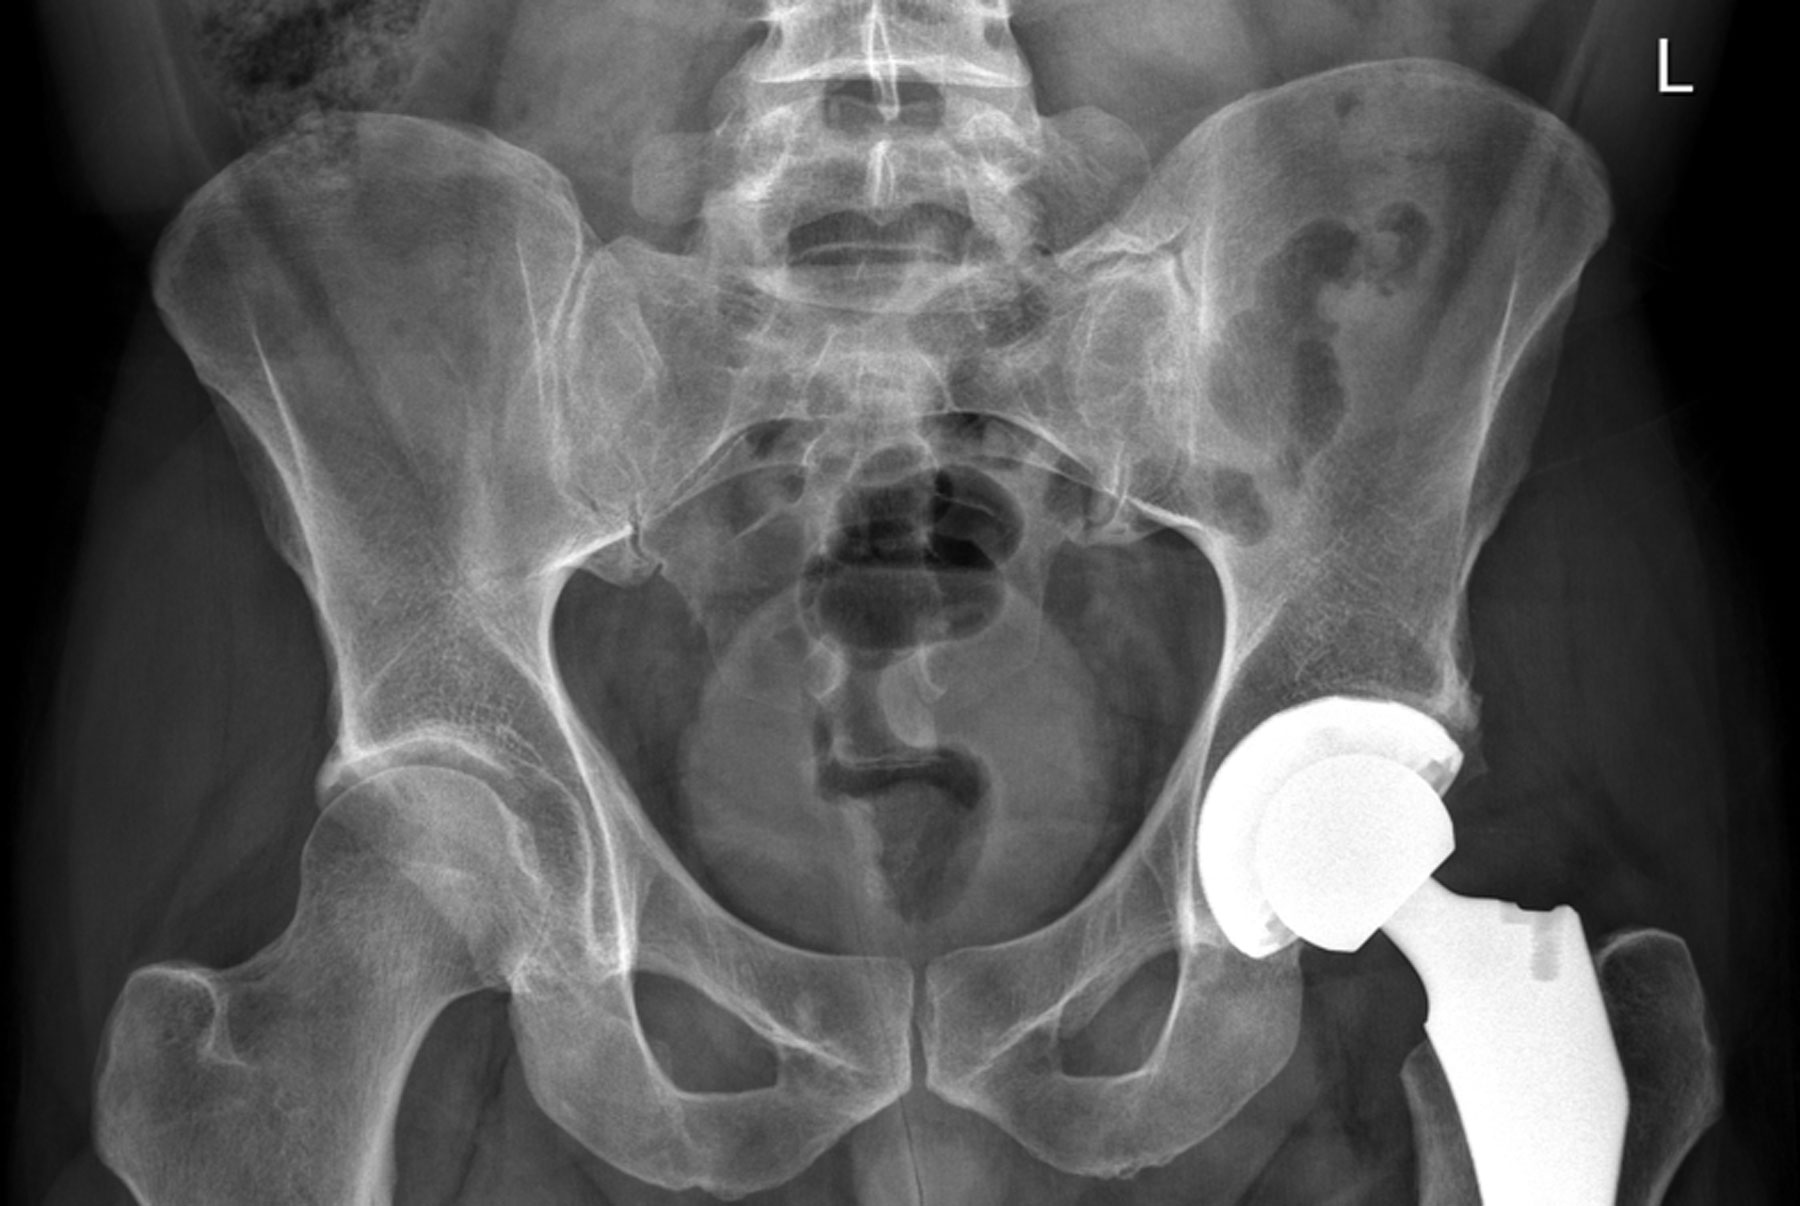

Rob Verger Hip X-Ray

The author’s new hip. He received a Smith & Nephew prosthesis, while the implant in the image at the top of the article is an Austin Moore device from the 1950s. NYU Langone